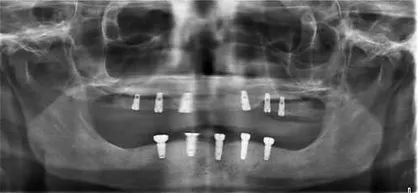

Dental implants are small metal or titanium posts that are designed to function like a natural tooth root. Placed carefully in the space left by a missing tooth, a dental implant is securely anchored to the jawbone. Over time, the implant is expected to merge with the bone becoming a permanent part of the mouth, just like a natural tooth.

A Customised Dental Crown Is Then Placed On The Implant To Provide The Finishing Touch. Our clinic utilises the latest technologies and dental expertise to make sure that the dental implant feels, looks and functions like a natural tooth. In fact, it may be difficult to distinguish between the dental implant itself and your real teeth.